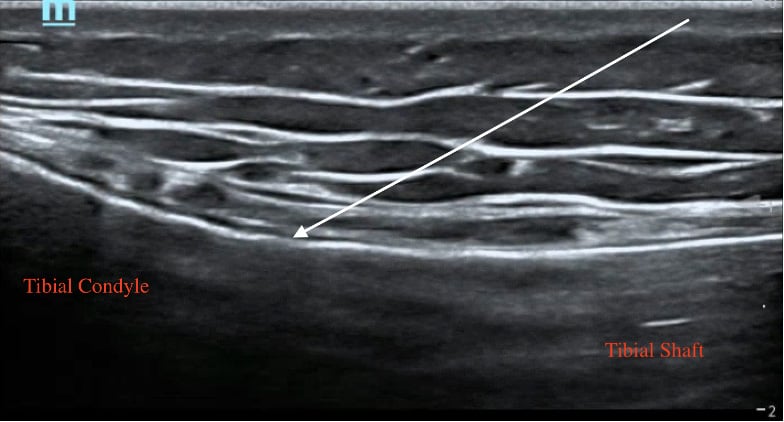

To block the IMGN, place the linear probe on the superomedial aspect of the tibia and identify the tibial shaft and medial condyle. Place color Doppler where the shaft slopes up to become the condyle and identify the inferior medial genicular artery. Advance the needle toward the knee making contact with the shaft as it slopes upwards and inject 3-5 mL of local anesthetic.

Figure 4: Tibial ultrasound anatomy with arrow indicating needle trajectory